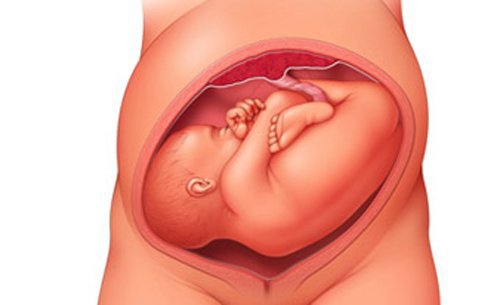

Nội xoay thai có nghĩa là xoay thai trong buồng tử cung, tiến hành khi đẻ và thường được thực hiện khi đẻ thai thứ hai của cuộc chuyển dạ sinh song thai. Nội xoay thai là kỹ thuật để chuyển ngôi thai nhi từ ngôi bất thường thành ngôi thuận để có thể sinh được bằng đường âm đạo. Chỉ định nội xoay thai khi tiên lượng sản phụ có thể sinh thường, thai nhỏ và thai nhi nằm ngang trong tử cung mẹ. Mục đích của nội xoay thai là biến ngôi thai từ ngang chuyển thành ngôi thuận để cho thuận lợi trong việc sinh thường.

Kỹ thuật nội xoay thai chỉ được thực hiện trong chuyển dạ, khi cổ tử cung mở hết thai đôi thứ hai là ngôi ngang và cần thực hiện ở các cơ sở y tế có đầy đủ trang thiết bị và đội ngũ y bác sĩ có thể hồi sức cấp cứu cho mẹ và bé để đảm bảo an toàn về sức khỏe của cả mẹ và bé.

TTYT huyện Yên Lập đã triển khai thực hiện thành công nhiều ca đỡ đẻ với kỹ thuật nội xoay thai. Điển hình là những ca sinh đôi 1 ngôi đầu và 1 ngôi ngang. Ngày 16/9 vừa qua, sản phụ P.T.N mang song thai 36 tuần 2 ngày, nhập viện với tình trạng có cơn co tử cung TS 3’/30’’, cổ tử cung mở hết, 1 thai ngôi đầu và 1 thai ngôi ngang. Trước đó sản phụ đã sinh thường 2 lần, các bác sỹ khoa Phụ Sản tiên lượng sinh thường được nên đã tư vấn, thống nhất với sản phụ và gia đình thực hiện phương pháp nội xoay thai với thai nhi số 2. Sau 30 phút, 2 bé gái kháu khỉnh đã chào đời bình an, da hồng hào, nhịp thở đều, phản xạ sơ sinh đáp ứng tốt, sản phụ tỉnh táo, tử cung co hồi tốt. Sau sinh 2 ngày, sản phụ và sơ sinh đều ổn định nên đã được xuất viện.

Nội xoay thai là phương pháp giúp sản phụ có thể sinh thường, tránh phải thực hiện cuộc phẫu thuật lấy thai, do đó sản phụ có thời gian phục hồi nhanh hơn. Do sơ sinh đi qua ống sinh dục của người mẹ, được ống sinh dục của người mẹ co bóp lồng ngực, nên sẽ giúp trào hết dịch tiết trong phổi với phế nang.